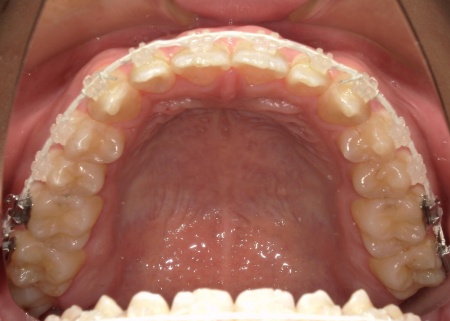

患者様は「できるだけ目立ちにくい装置を使用したい」とのことから、②のセラミックブラケット矯正を選択されました。

まず、下奥歯(臼歯)を歯茎の外側に持ち上げる「挺出(ていしゅつ)」という処置を行いました。

奥歯が少し高くなることで、下顎全体がわずかに後ろへ動くため、前歯の噛み合わせが整いやすくなります。

加えて、上下の前歯には「IPR」という処置を行いました。これは、歯の表面のエナメル質をごくわずかに削り、歯を動かすためのスペースを作る方法です。

このスペースを利用して前歯を後方へ移動させ、審美性の改善を目指しました。